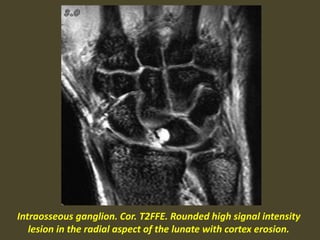

Intraosseous ganglion. Cor. T2FFE. Rounded high signal intensity

lesion in the radial aspect of the lunate with cortex erosion.